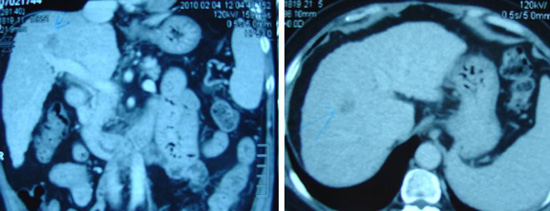

- CT scan on 5 March 2003, showed a 3.3 cm well-defined simple cyst in Segment 1 of her liver. In the upper pole of her right kidney was a 2.4 cm enhancing nodule with exophytic component.

- A 3.4 x 3.3 cm cyst in the right lobe of her liver.

- MRI of her abdomen done on the same day confirmed the presence of a 2.5×1.6×2.5 cm, irregularly enhancing mass in the upper pole of her right kidney with features suggestive of an underlying renal cell carcinoma.